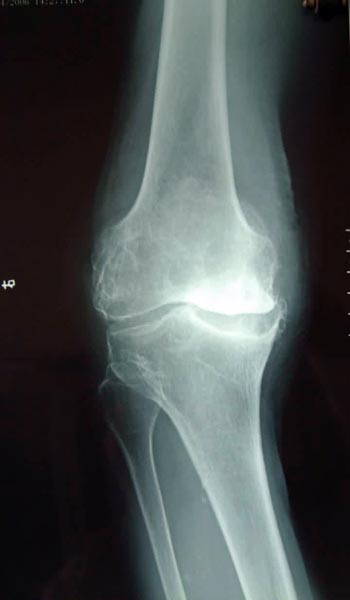

患者严重膝骨关节炎,关节软骨破坏,明显疼痛,行走困难